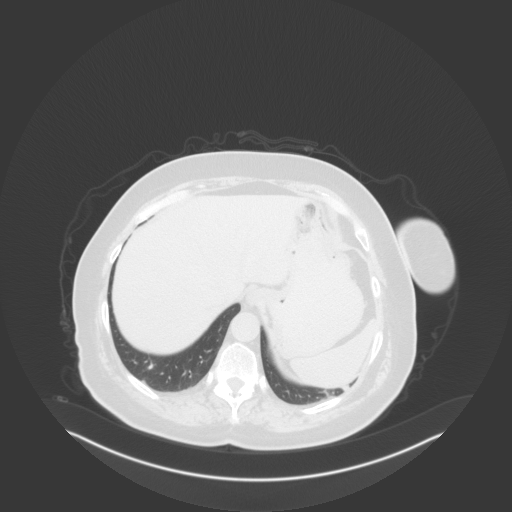

Original NATIVE CT scan (input)

Full window (WL 1023.5, WW 4095 β†’ Low βˆ’1024, High +3071)

Original VENOUS CT scan

Generated VENOUS CT scan (A→B translation)